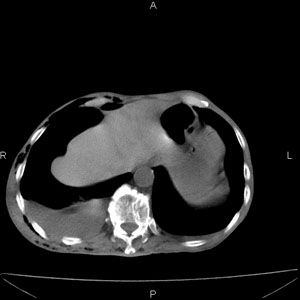

患者男,77岁,于3日前从树上摔下,头部查ct示蛛血,硬膜下出血,上腹部ct未见明显异常,右侧胸腔积液,左侧如常。肺部拍片示右侧肋骨多发骨折住院后今日来查肺部ct,我看到的是1。右侧胸腔血气胸并右肺上叶,中叶压缩性肺不张,2。右肺下叶肺挫伤并多发肋骨骨折,肌内及皮下积气3。左侧少量胸腔积液,我想请教的是3天前左侧胸腔里没有积液今天怎么出现了呢,是什么原因呢?请讨论。

右侧液气胸,胸膜创伤、肺组织挫伤,渗出属正常反应。

右侧多发肋骨骨折,同侧液气胸